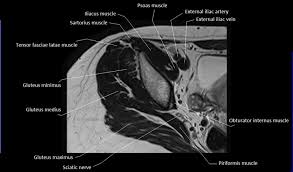

Some of the most important include … The ligament around this joint relaxes during pregnancy. This section of the website will explain large and minute details of axial male pelvis use the mouse scroll wheel to move the images up and down alternatively use the tiny arrows (>>) on both side of the image to move the images. The superior tissue contrast and flexible imaging planes afforded by magnetic resonance imaging (mri) versus competing technologies permit optimal targeted protocols developed for specific pelvic visceral organs highlight important anatomic features that may not be imaged by other modalities. Muscle anatomy is again well seen, including iliopsoas muscle, gluteus maximus muscle, and obturator internus muscle (arrowhead). Mri pelvis anatomy | free male pelvis axial anatomy from mrimaster.com start studying mri anatomy pelvis. It is strengthened and supported by several joints and ligaments. Mri anatomy and positioning series module 5: Muscles of the pelvis that cross the lumbosacral joint to attach onto the trunk were described in the previous blog post note: The pelvic region holds major organs under its layers of muscles. The pelvic girdle differs from other bony anatomical regions because it protects and supports abdominal and pelvic organs. Functional anatomy of the pelvis, sacroiliac joint and lumbar spine. The vital shoulder complex 6.